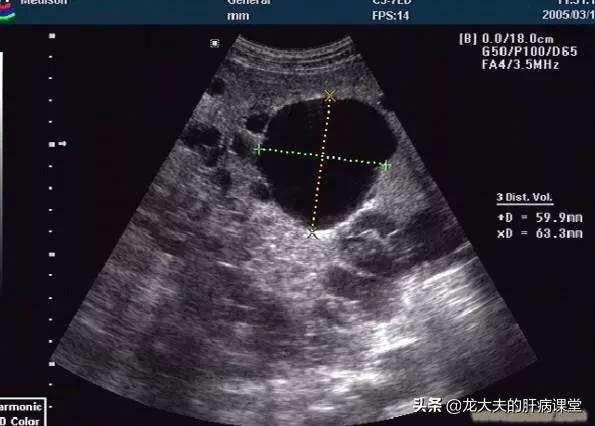

このタイプの肝嚢胞は良性病変であり、通常は明らかな臨床症状がなく、超音波検査やCT検査で偶然発見されるだけである。また、患者に腹痛や腹部不快感を引き起こす一部の大きな嚢胞だけが、通常女性に多い。

多発性肝嚢胞の肝機能の検査は一般的に正常であり、肝臓領域の超音波検査では、1つ以上の液体の安全性を見ることができます。 CTまたは核スキャンはまた、多発性肝嚢胞があるかどうかをチェックすることができ、さらに多発性肝嚢胞は実質的な病変がないことを決定することができます。